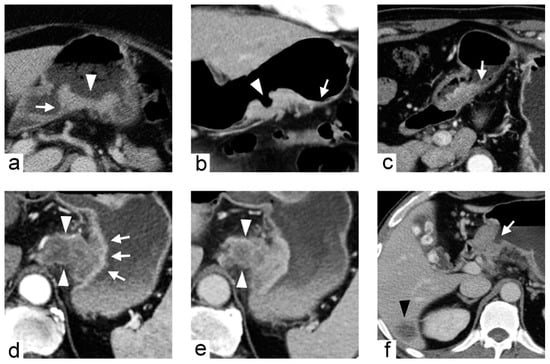

Figure 5. Imaging traits of gastric cancers demonstrated in different patients. (a) 71-year-old female with gastric cancer at posterior wall of gastric body. Contrast-enhanced computed tomography (CT) during portal venous phase axial image demonstrates the tumor with fungating shape (arrowhead), well-defined margin and acute tumor transition angle (arrow). (b) 61-year-old female with gastric cancer at greater curvature of gastric body. Contrast-enhanced CT during arterial phase coronal image demonstrates the tumor with ulcerative shape (arrowhead), ill-defined margin and obtuse tumor transition angle (arrow). (c) 66-year-old male with gastric cancer at antrum. Contrast-enhanced CT during arterial phase axial image demonstrates the tumor with polypoid shape, ill-defined margin and obtuse tumor transition angle (arrow). (d,e) 73-year-old male with gastric cancer at cardia. Contrast-enhanced CT during arterial phase (d) and portal venous phase (e) axial images demonstrate the tumor with an inner layer of higher contrast enhancement (arrows in (d)) and an outer extra-gastric portion of heterogeneously lower contrast enhancement (arrowheads in (d,e)). (f) 56-year-old male with gastric cancer at antrum. Contrast-enhanced CT during arterial phase axial image demonstrates the tumor with luminal obstruction (arrow) and liver metastasis (arrowhead).